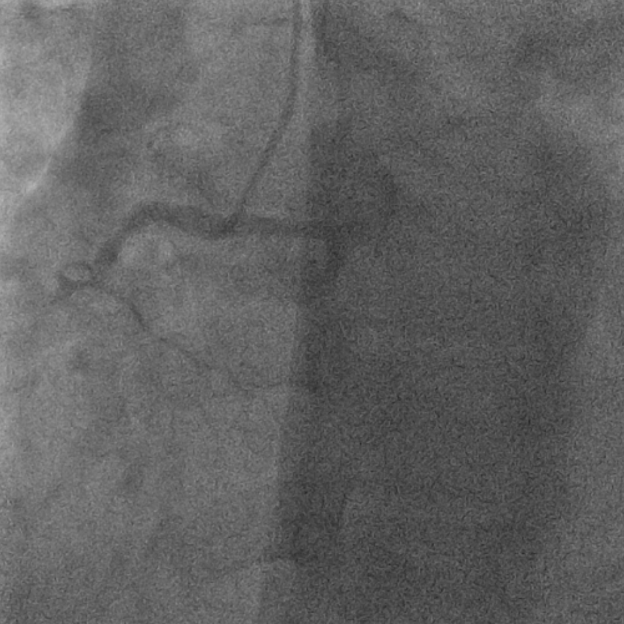

抽吸【例】量|【李】解抽吸患者获益